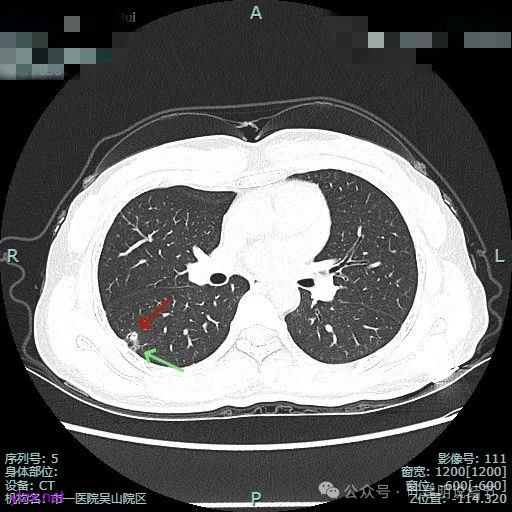

非薄层平扫上这个层面比较明显,似一囊腔,壁厚薄欠均匀。

薄层上看病灶贴着叶间裂与胸膜,此层囊壁薄,囊腔明显。

囊壁局部有增厚。

囊壁局部较厚,但囊壁内也是有小空泡的,病灶贴着胸膜。